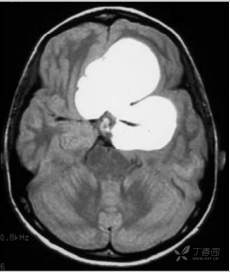

图9.13 头部非增强轴位CT显示梗阻性脑积水(脑室扩张)

图9.14 脑部轴位液体衰减反转恢复磁共振成像显示一个大的脑肿瘤,其占位效应导致颅内压升高。